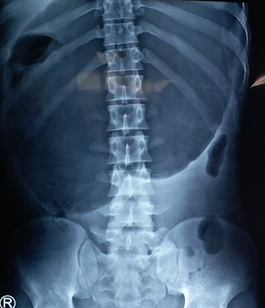

Peritoneovenous shunt in another patient with decompensated hepatic cirrhosis (Courtesy Dr. V. Penopoulos)